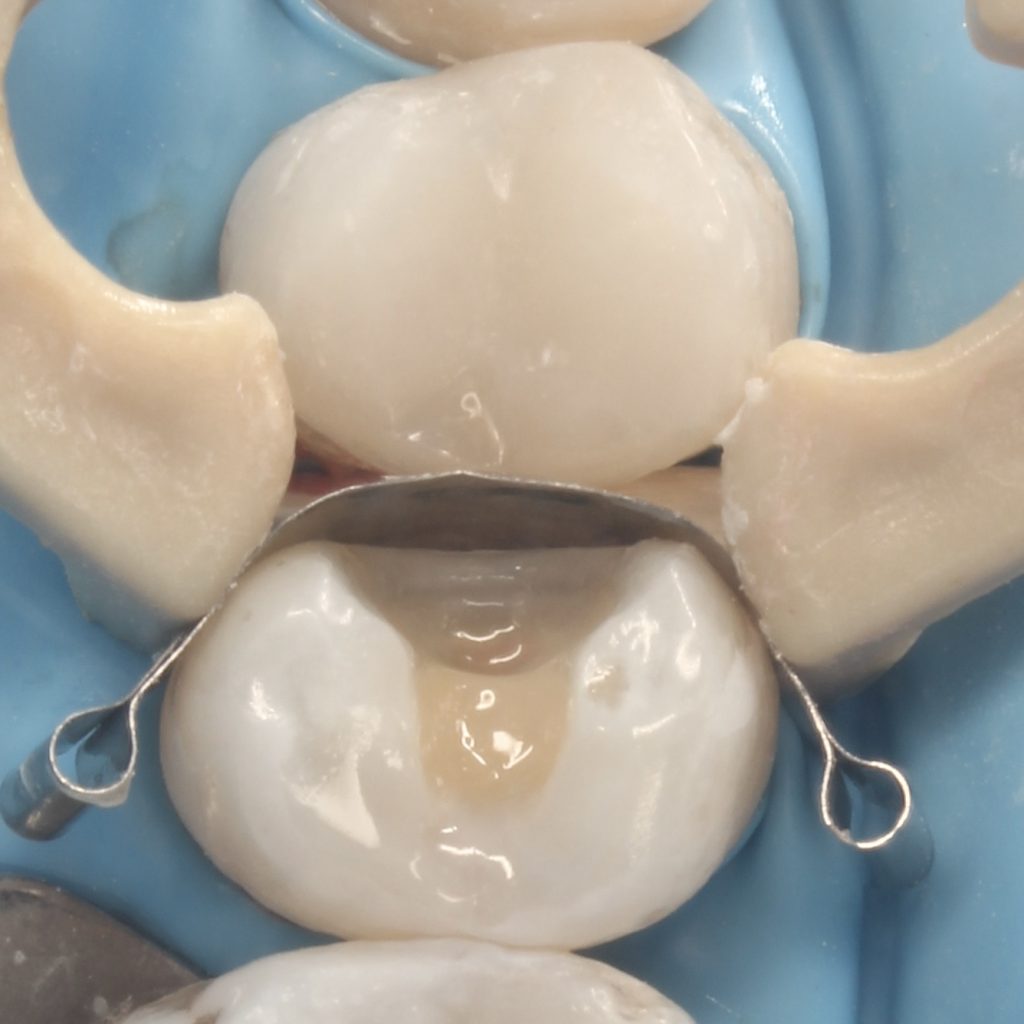

A 22 years old patient came to the clinic suffering from severe spontaneous pain. The diagnosis was acute irreversible pulpitis. The use of CDD is crucial here to ensure the CRE. After finishing endodontic treatment we used polyethylene fibers to enhance the bond strength and the strength of the tooth. Then the use of glass fibers (ever X composite) as a dentin replacement material before the final layer. After finishing. Polishing protocol with eve twist was done to gain the final polish